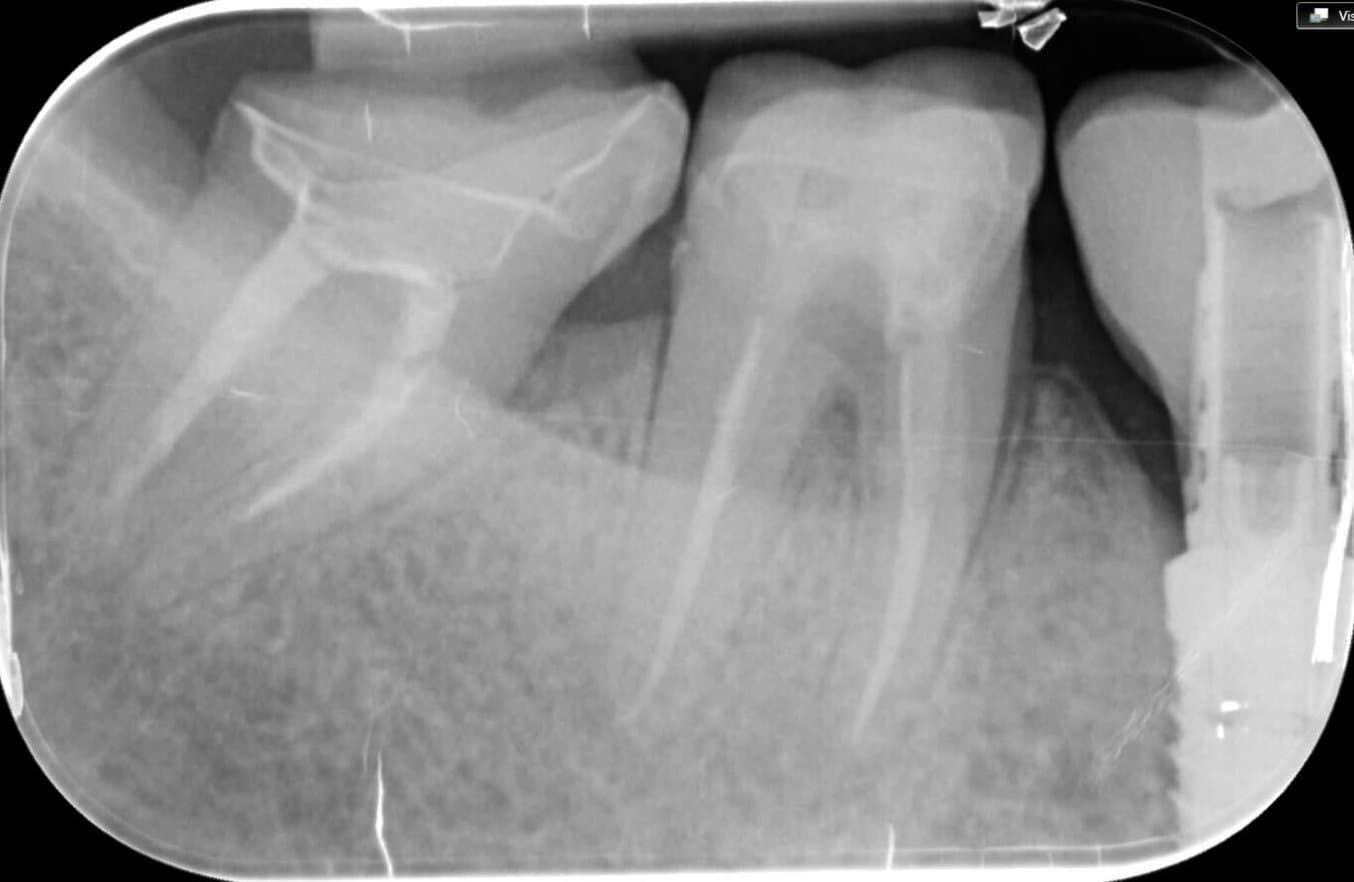

Dr. Cacioppo appreciates that restorations printed with BEGO™ VarseoSmileⓇ TriniQⓇ Resin are radiopaque, making them clinically visible on X-rays. However, in accordance with ISO standards, its radiopacity is below the specified threshold.